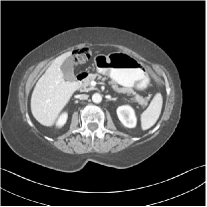

III.C.2. Simulation Framework, Reconstruction Results, and Comparisons

The synthesized low-dose clinical measurements are simulated from regular-dose images at a resolution of mm with a fan-beam CT geometry corresponding to a monoenergetic source at incident photon intensity . The sinograms are of size . The width of each detector column is mm, the source to detector distance is mm, and the source to rotation center distance is mm. We reconstruct images of size with the pixel size being mm mm.

We conducted experiments on one test slice used for parameter tuning (L067-slice 120) and four independent test slices (L109-slice 90, L192-slice90, L333-slice140, L506-slice 100) of the Mayo Clinic data. For PWLS-EP, we ran iterations using relaxed OS-LALM and set regularization parameter . We used the same as the phantom experiments for Algorithm 2. The process of selecting a general set of reconstruction parameters () for the Mayo Clinic test slices is identical to that for the XCAT phantom in Section III.B.2. The selected regularization parameter and the parameters that control the sparsity of the coefficient maps are for ST, , , , , for MARS2, , , , , , , for MARS3, , , , , , , , , , , for MARS5, and , , , , , , , , , , , , , , for MARS7, respectively.

Figs. 8, 9, 10, and 11 show the reconstructions of the four independent slices using the FBP, PWLS-EP, PWLS-ST, PWLS-MARS2, PWLS-MARS3, PWLS-MARS5, and PWLS-MARS7 schemes, respectively. Additional Mayo Clinic experimental results of the parameter tuning case (Fig. 15) are shown in the supplementary document. Table 1 lists the RMSE and SSIM values of reconstructions of the four independent test slices, with the best values bolded. Generally, the five and seven layer models provided the best RMSE and SSIM values. They outperform the single-layer model by HU in RMSE on average. However, the MARS5 and MARS7 models perform similarly. In order to strengthen the benefits of the multi-layer model, Table 2 lists the RMSE of the reconstructions in four different ROIs (shown in the reference of Fig. 11) with seven methods for slice 100 of patient L506. By observing the reconstructed images, we see that although the ST model achieves a cleaner reconstruction result than FBP and PWLS-EP, it still sacrifices some sharpness of the central region and suffers from loss of details. The deeper models have a somewhat more positive effect in terms of maintaining subtle features, which is clearly more essential to clinical diagnosis. Furthermore, as we will discuss later, after considerable parameter tuning, we found that the information contained in residual maps is gradually decreased with the number of layers, eventually vanishing at some layer, which suggests that very deep unsupervised models might not offer significantly better image quality.